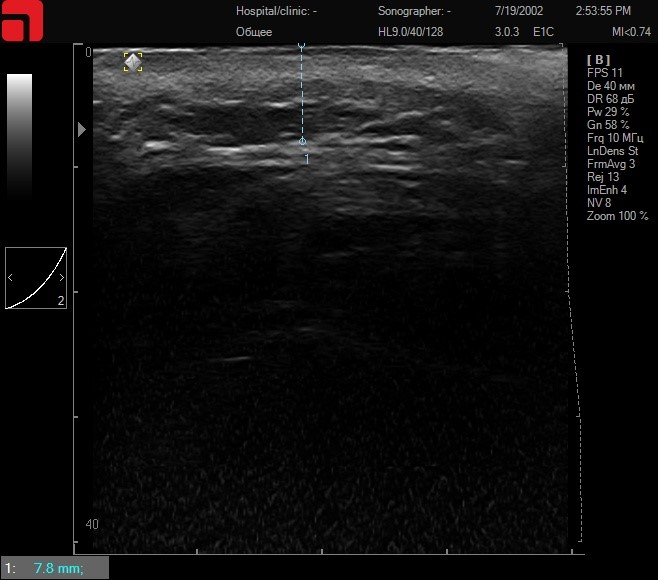

Все сканограммы сделаны у одного пациента из одной точки сканирования – средняя часть щечной области.

Соединительная ткань при умеренном надавливании в щечной области

Рис. 1. Соединительная ткань при умеренном надавливании в щечной области.

На данном снимке видно, что у данного пациента SMAS-слой расположен глубоко, с такой интенсивностью надавливания лифтинговые насадки будут работать с соединительной тканью в ПЖК, но существенно повлиять на SMAS-слой не получится, следовательно, эффективность от такого проведения процедуры будет снижена.